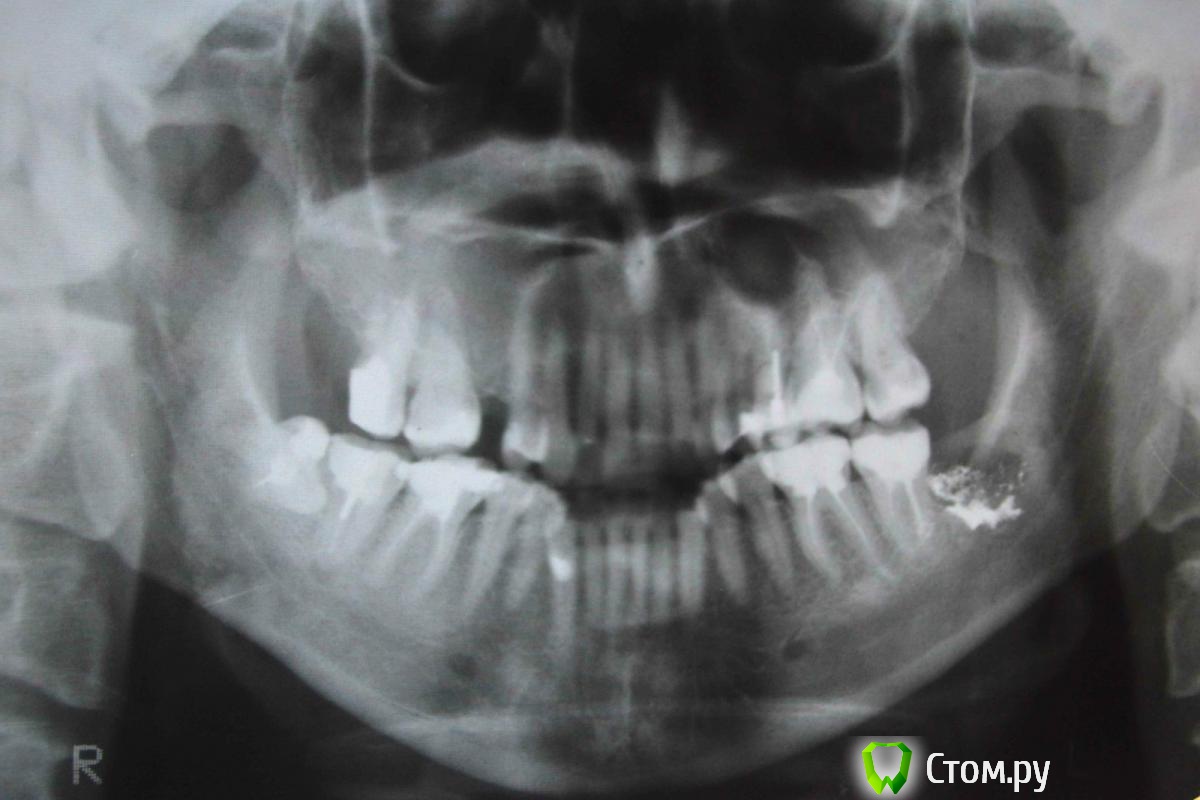

Evelyn Опубликовано 13 ноября, 2014 Поделиться Опубликовано 13 ноября, 2014 Здравствуйте!В хирургии уже писала по поводу удаления 38-го, поэтому на него на снимке можно не обращать внимания)))Сейчас жую, соответственно, пока на противоположной стороне. Начали при сжимании зубов побаливать 16 и, кажется, 47. И немного отдает в ВЧС (но при удалении 38 челюсть пару раз выскакивала). Видно ли этой ОПТГ что-нибудь с этой стороны? Ссылка на комментарий

red_butler Опубликовано 13 ноября, 2014 Поделиться Опубликовано 13 ноября, 2014 4.7 4.6 повторное лечение корневых каналов и протезирование, 1.6 на снимке плохо видно. 4.8 удалять. 1.7 прицельный снимок 1 Ссылка на комментарий

shishok Опубликовано 13 ноября, 2014 Поделиться Опубликовано 13 ноября, 2014 27 зуб-похоже на кариес на передней поверхности. Ссылка на комментарий